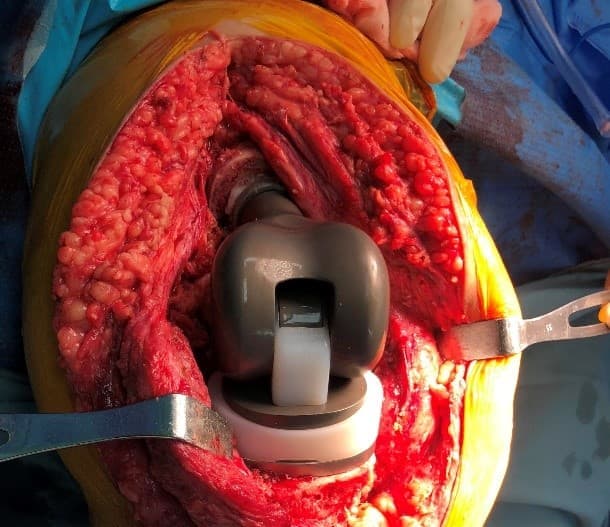

Үе дайрсан ясны анхдагч хавдар, ясны дутмагшлын үед хийгдэх мэс засалimage33

Зураг 2. Мэс заслын үеийн фотозураг. Өвдөгний хиймэл үе – сэргээн засах протез

Энэ хиймэл үений онцлог нь дунд чөмөгний гандан хэсгийн доод 1/3 хэсэг, үений булуу хэсгийг бүрэн орлох хавдрын тусгай хиймэл үе юм. Мөн hinge system-тэй.